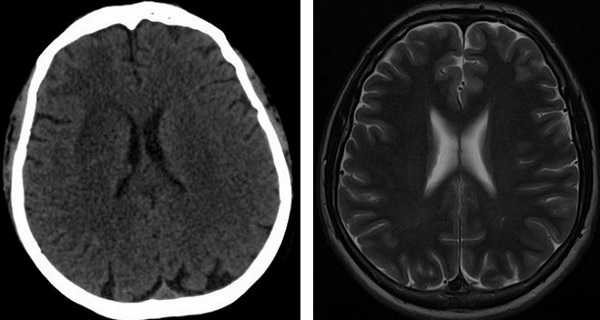

Оба диагностические исследования дают ценную информацию врачу. Содержимое головы изучают в виде серии снимков или трехмерного изображения. КТ основана на ионизирующем излучении (рентгеновском), поэтому ее не назначают беременным и маленьким детям. На снимках, полученных при компьютерной томографии, хорошо видны кости, отложения солей кальция на месте воспаления или опухоли, свежие очаги кровоизлияния (до 6 часов). В некоторых больницах нет магнитных томографов, назначают проведение КТ с контрастом. КТ станет методом выбора, если пациент имеет травмы черепа, симптоматику свежего геморрагического инсульта, при паразитарных кистах в мозге, очагах обызвествления.

КТ головного мозга МРТ головного мозга

В остальных случаях более информативной будет МРТ. Особенно ценная МРТ при болезнях мозжечка, стволовых структур мозга, при ишемическом инсульте, разрушении миелиновой оболочки нервов, психических болезнях. При отсутствии аппарата диагностику проводят теми методами, которые доступны, - УЗИ, рентген, КТ, ангиография, ЭЭГ, РЭГ.